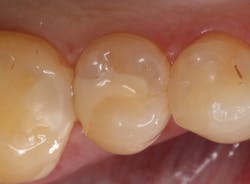

I have found that most posterior teeth can be restored using a single shade. In cases where the tooth structure is very discolored, coupled with a shallow tooth preparation, I opt for an opaque layer beneath my core shade. For anterior cases, the enamel shades offer enough translucency to give the restoration a lifelike appearance. I tend to opt for a core shade to restore chipped incisal edges, and the results have been terrific. Nothing’s worse than a patient coming back with an anterior composite restoration that didn’t hold up; it leads to patients losing confidence in your skills, sometimes negative reviews, wasted chair time, and lost profitability. Polishing this composite is very efficient and effective, and so far, it’s maintained its shine. From my assistants’ perspectives, simplifying my systems made it easier to learn, maintain inventory, and prepare for direct restorations. From my perspective, simplifying composite restorations allows me to reduce chair time, minimize waste, and predictably and efficiently place restorations that my patients love.

Fabricating composite restorations with a simplified system can yield exceptional clinical outcomes and enhance practice profitability.

Results